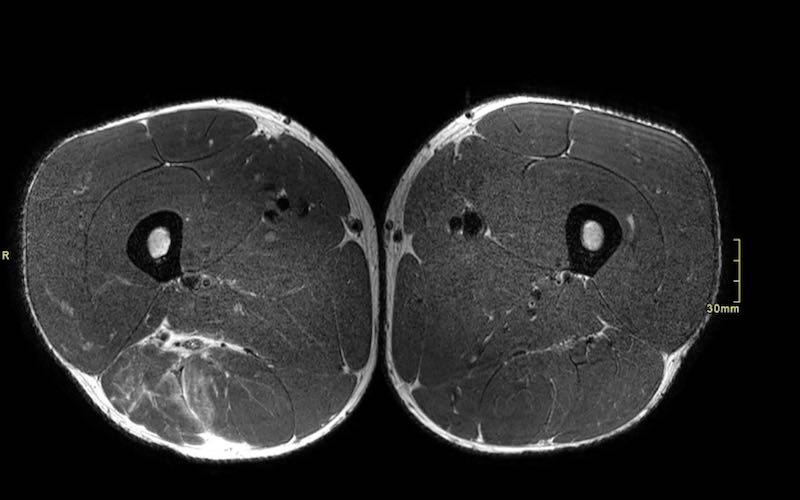

Mặt phẳng coronal so với mặt phẳng axial

Chỉ dựa vào các hình ảnh coronal đơn thuần, đôi khi khó có thể phân loại chính xác mức độ biến dạng. Cần sử dụng các hình ảnh axial để quan sát kỹ hơn.

Trên các hình ảnh axial này, có thể thấy tăng tín hiệu và dày lên của gân cơ nhị đầu đùi bên trái (vòng tròn chấm vàng) khi so sánh với bên không bị tổn thương (vòng tròn chấm trắng).

Toàn bộ phức hợp cơ hamstring của cả hai chân cần được khảo sát trên tất cả các chuỗi xung để so sánh bên tổn thương với bên hamstring lành.